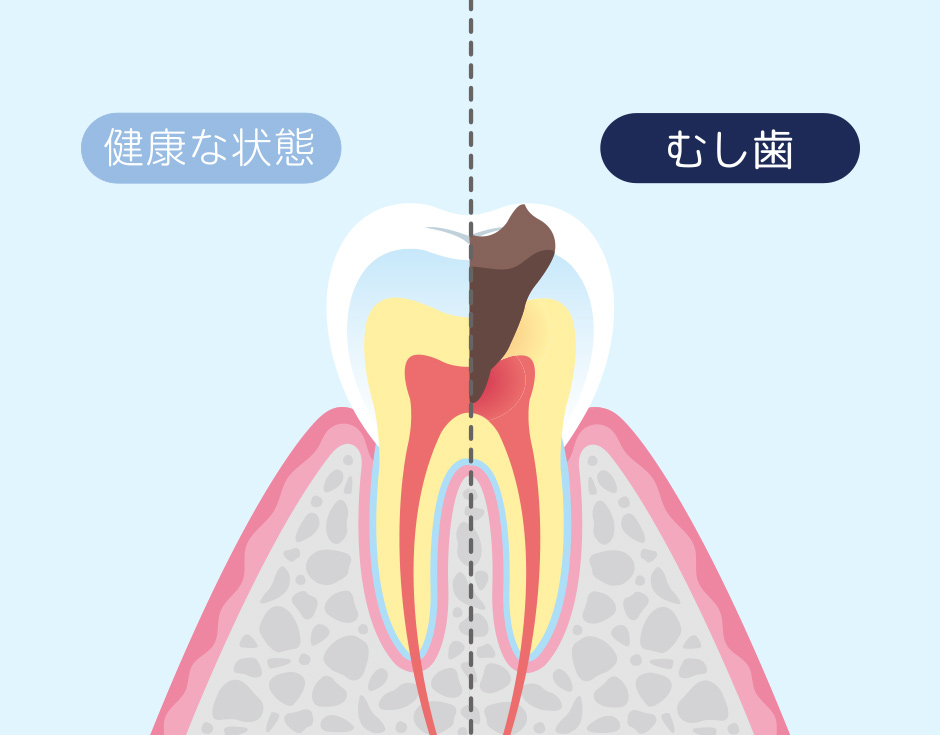

歯に穴が開いてしまう疾患

口腔内の糖分を餌に繁殖したミュータンス菌などのむし歯の原因菌が酸を放出し、歯のカルシウムを溶かして穴を空けてしまう病気です。最初は表面のエナメル質を溶かしますが、進行すると象牙質や歯髄にまで進行してしまいます。